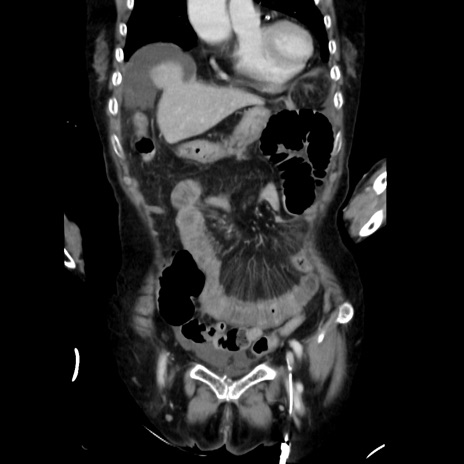

症例40(冠状断像)

【症例】90歳代女性

【主訴】腹痛・嘔吐

【現病歴】 食欲低下、嘔吐があり昨日他院受診。肺炎と診断され入院となる。入院後より腹部全体に圧痛あり。胃管留置され経過みていたが、症状持続するため、

当院転院となる。

【既往歴】胸椎圧迫骨折、胆石症

【身体所見】腹部:中央に激痛あり、圧痛あり、反跳痛不明

【データ】WBC 17100、CRP 18.82

冠状断像